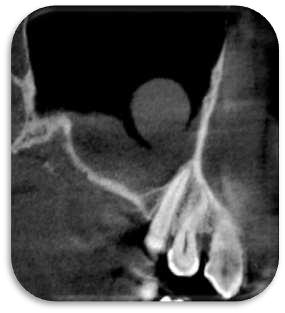

RECONSTRUCCION 3D DE LA ZONA A ESTUDIAR

Las reconstrucciones tridimensionales nos permiten una visualización detallada y precisa de las estructuras vecinas a la pieza retenida, superando las limitaciones 2D de las radiografías convencionales, también ayudara en este caso para la planificación quirúrgica y posterior tratamiento de ortodoncia.

En este caso podemos observar una lesión de diámetro considerable de bordes corticalizados y forma irregular proyectada en el maxilar superior en el cuadrante 1, que se extiende desde distal de la pieza 1.1 hasta distal de la pieza 1.5, desde el tercio apical de las piezas 1.2 – 1.4 y 1.4 por vestibular y desde cervical por palatino. Se evidencia también a la pieza 1.3 retenida desplazada el ápice hacia la cortical palatina y la corona hacia la cortical palatina

CORTES AXIALES

Con la evaluación de la tomografía volumétrica en cortes axiales y transversales se observa la expansión y adelgazamiento de la tabla ósea vestibular y palatina legando a dicha pérdida ósea, también se observa el desplazamiento de la pieza 1 3 la cual se encuentra retenida y desplazada hacia la basal vestibular.

CONCLUSION

CORTES SAGITALES

A nivel de los cortes sagitales y coronal verificamos la extensión de la lesión y evidenciar el desplazamiento de las piezas 1.2 a mesial y 1.4 hacia distal a causa de la retención de la pieza 1.3 y expansión de la lesión